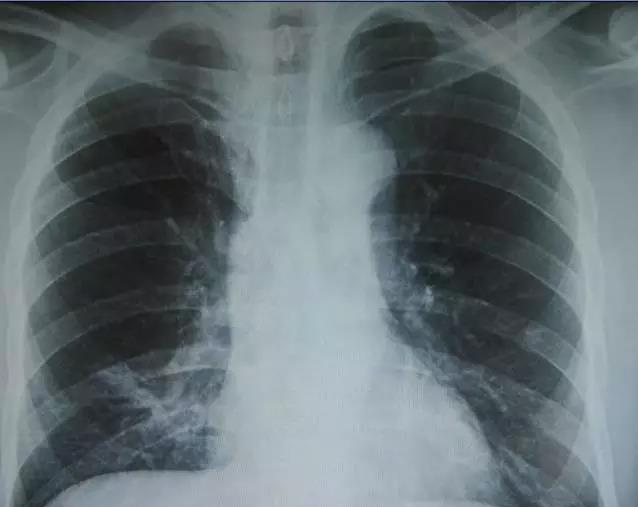

X光是穿透性很强的射线,能够穿透人体,使用X线对人体内部进行透视或摄影的检查方法,其原理是利用了X线的穿透作用。在穿透人体时,被含钙的成分(骨)、水分(血液等)、软组织(肌肉)等吸收而减弱,X线会穿过人体,遇到被遮挡的部位,底片上不会曝光,洗片后这个部位就是白色的。因此可以呈现出所检查部位的基本形态。

就像一片面包或一块棉花,看不到里面的纤维纹理,但用手压瘪了会清晰一些。X线最大缺点是受制于深浅组织的影像相互重叠和隐藏,有时需要多次多角度拍摄X线片。

X线胸片可粗略检查心脏、主动脉、肺、胸膜、肋骨等,可以检查有无肺纹理增多、肺部钙化点、主动脉结钙化等。

胸部CT检查显示出的结构更清晰,对胸部病变检出敏感性和显示病变的准确性均优于常规X线胸片,特别是对于早期肺癌确诊有决定性意义。但是CT检查的辐射剂量高于X线。核磁对于肺部疾病的诊断,应用非常有限。